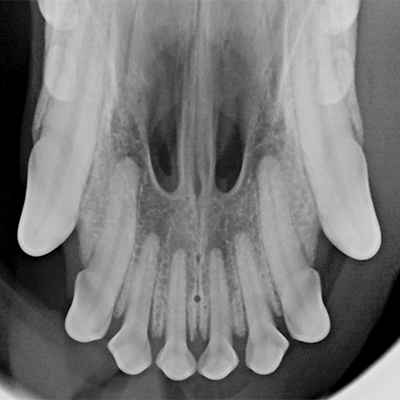

• Digital dental X-rays

• Ultrasonic scaling above & below the gumline

• Tooth extractions if medically necessary